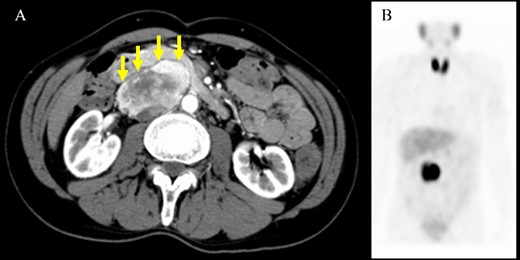

A 61-year-old man underwent a positive fecal occult blood test and was diagnosed with adenocarcinoma of the transverse colon based on colonoscopy and biopsy results. During the preoperative evaluation, a hypervascular neoplasm located posterior to the pancreatic head was incidentally detected on abdominal contrast-enhanced CT scan (Fig. 2A). The arterial phase of the contrast-enhanced CT scan showed a 6.5 × 3.5 cm2 heterogeneous mass with fat plane between the mass and pancreas while a beak sign was not observed. The patient’s medical history included hypertension, and PGL was suspected based on CT scan images and medical history. His laboratory data were unremarkable except for high urinary metanephrine levels. Metaiodobenzylguanidine (MIBG) scintigraphy was also performed and showed an abnormal uptake at the site of the neoplasm (Fig. 2B). Thus, the patient was preoperatively diagnosed with PGL. According to the intraoperative findings, combined resection with pancreatectomy was unnecessary (Fig. 3). Hence, he underwent tumor resection for PGL and right hemicolectomy for transverse colon cancer. Histopathological and immunohistochemical findings confirmed the diagnosis of PGL (Fig. 4). The patient had an uneventful course except for a mild superficial surgical site infection (Clavien–Dindo grade I complication), and no tumor recurrence was observed for 24 months.

Computed tomography scan and metaiodobenzylguanidine scintigraphy. (A) Imaging findings showing a well-defined mass with heterogeneous enhancement located adjacent to the pancreatic head. A fat plane was identified between the mass and pancreas (arrows). (B) Metaiodobenzylguanidine scintigraphy revealed accumulation at the same site of the abdominal tumor.